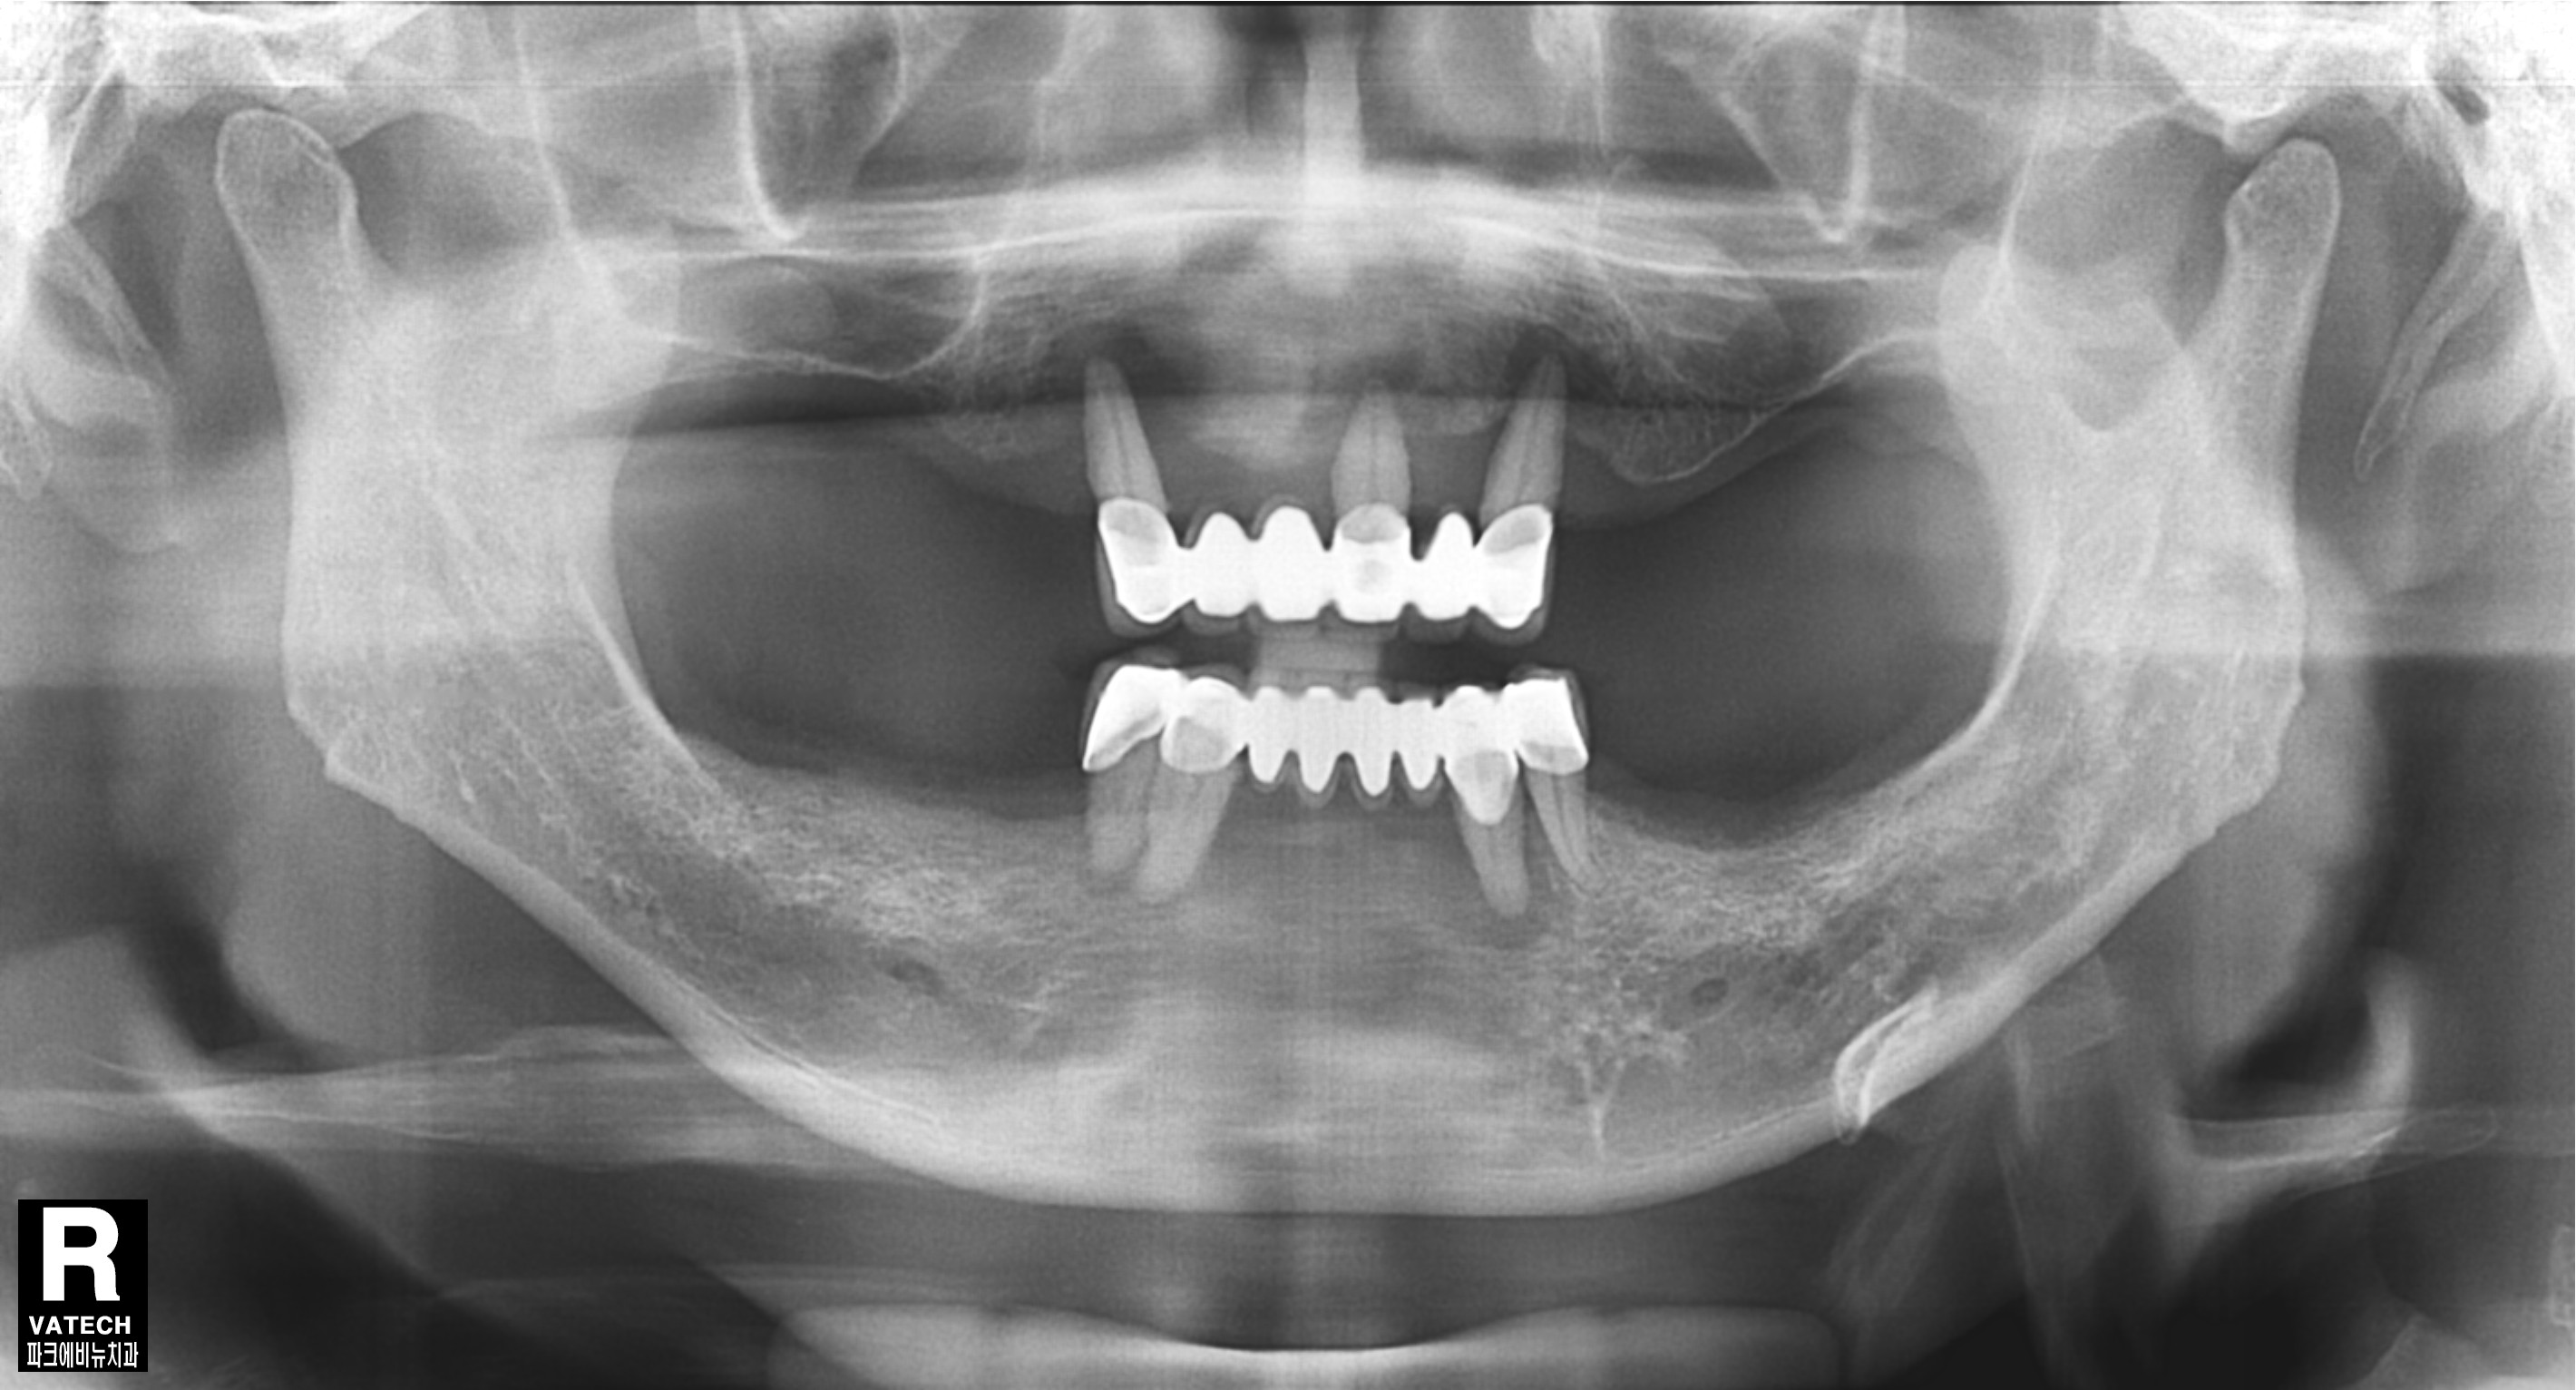

이 환자분은 위아래 틀니를 사용하시는 분인데 틀니를 거는 지대치인 앞니가 많이 흔들린다며

내원하셨습니다. 구강 내를 살펴보니 구강위생이 좋지 않아 치태,치석도 많고 잇몸이 많이 부어 있었습니다.

파노라마 방사선 사진도 살펴보면 치아를 잡는 치조골이 치아 뿌리 끝까지 많이 녹았음 확인할 수 있었습니다.

따라서 치아를 발치하고 전악 임플란트를 수복하기로 결정 하였습니다.